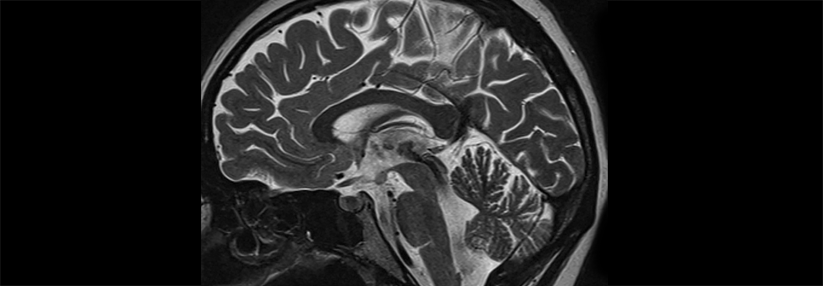

Ob riskantes Trinkverhalten oder manifester Alkoholabusus: Mittels funktionellem Magnetresonanztomographie-Neurofeedback trainieren betroffene…